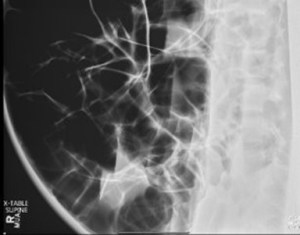

ED abdominal images and workup:

Significant lab results included a non-anion gap metabolic acidosis.

Figure 2. supine cross table abdominal plain film obtained in the ED.